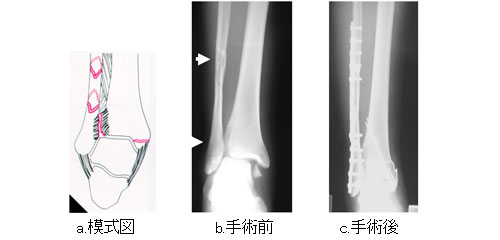

足関節骨折 一般社団法人 日本骨折治療学会 骨折の解説

足関節骨折 一般社団法人 日本骨折治療学会 骨折の解説

足関節骨折 一般社団法人 日本骨折治療学会 骨折の解説

足関節骨折 一般社団法人 日本骨折治療学会 骨折の解説

治療例 下肢 膝 足 保谷 骨折治療 川崎接骨院 交通事故の治療など